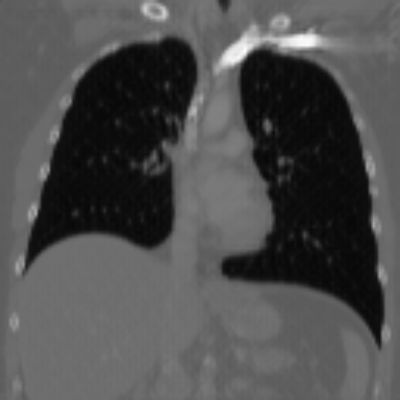

| Axial | Coronal | Sagittal | |

| X2CTGAN | ![]() |

![]() |

|

| DX2CT | ![]() |

| Ground-truth | ![]() |

Figure 3 and Table I(a) using biplanar X-rays show that proposed DX2CT can outperform three existing SOTA methods. Figure 3 shows that DX2CT can provide more accurate overall shapes and details compared to the existing methods. The quality of reconstructed CT slices in the axial plane is less satisfactory than those in the other planes. The reason is that the axial plane is perpendicular to the planes of biplanar X-rays so there exists less spatial (i.e., depth) information in the axial plane. Without using the perceptual loss [33], proposed DX2CT gave comparable LPIPS results with PerX2CTs using [33] in training. Compare their LPIPS results in Table I(a).